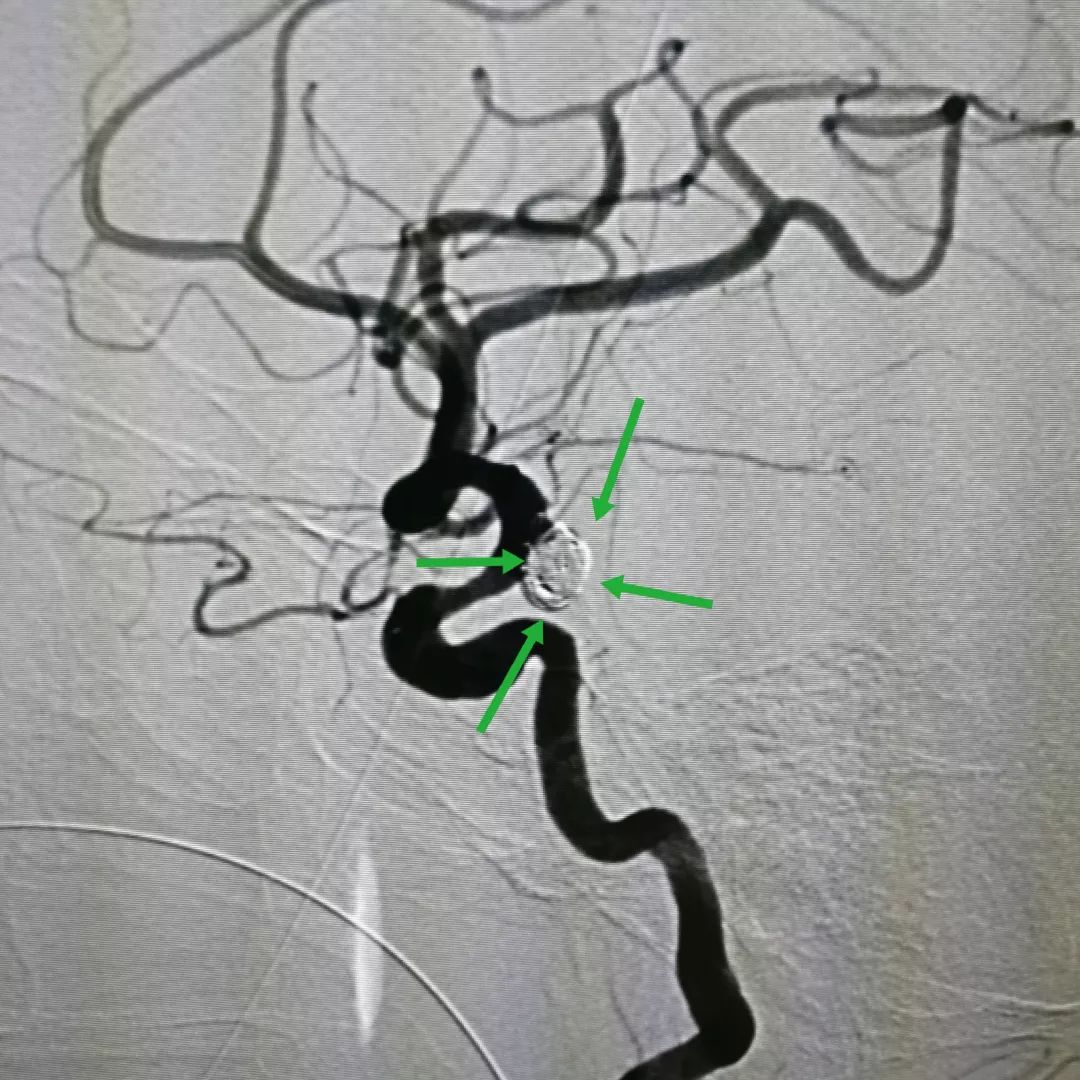

图四:介入栓塞手术中向动脉瘤内填塞弹簧圈堵住破口,防止再出血

图五:手术结束复查脑血管造影可以发现动脉瘤已被完全栓塞,瘤内无血液流入

图六:另一角度的术后造影片也证实动脉瘤完全栓塞